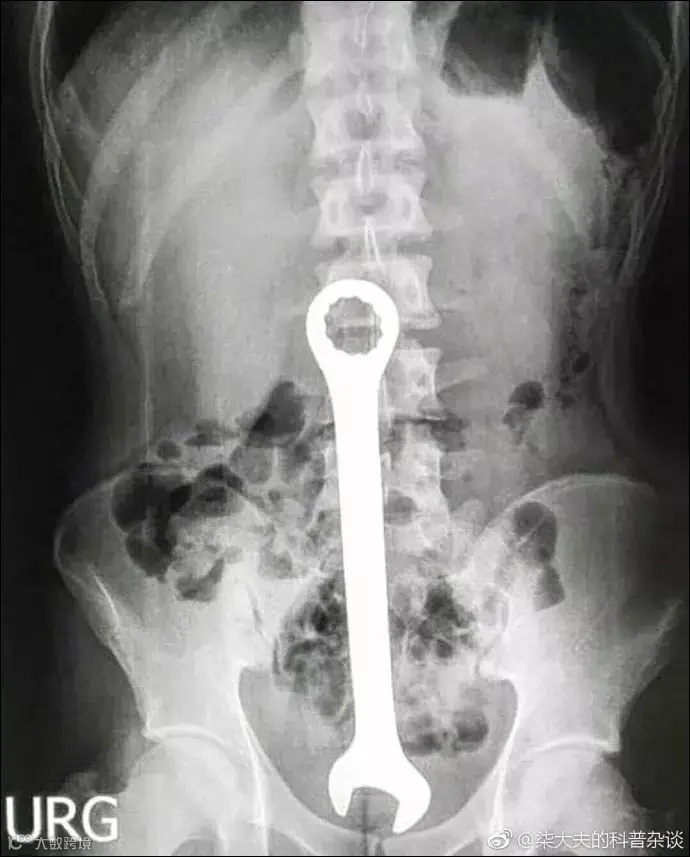

扳手▽